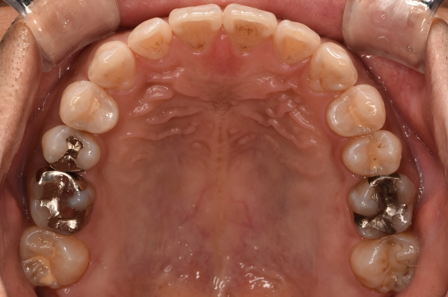

治療前

| カウンセリング・診断結果 | 診察したところ、上の前歯の真ん中に隙間が空いている状態でした(正中離開)。 |

| 行ったご提案・治療内容 | CTや3Dスキャンでの精密検査の結果、奥歯の噛み合わせ等には大きな問題はありませんでした。 そのため、インビザラインライトでの治療をご提案しました。 |